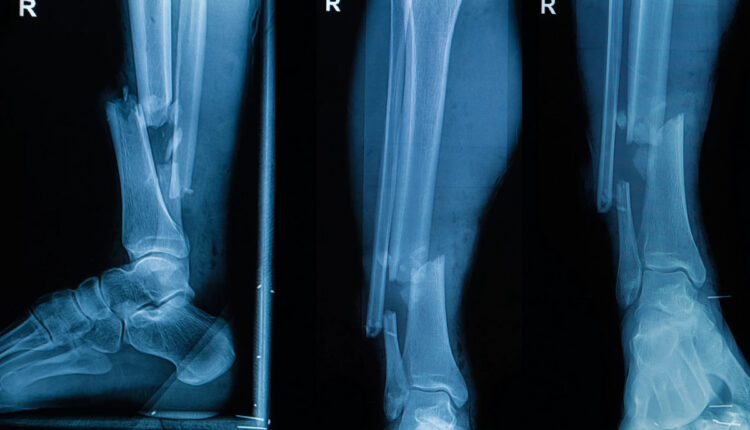

Группа ученых из США и Южной Кореи провела первые успешные испытания новой технологии по созданию костных имплантов непосредственно в месте повреждения костей. Они модернизировали клеевой пистолет, чтобы наносить специальный состав в нужную область в требуемых количествах. Он не заменяет собой кость, но позволяет устранить повреждения на время, пока костная ткань не разрастется и не заполнит этот участок.

Главное преимущество технологии в возможности отказаться от громоздких конструкций для фиксации обломков костей, а также сократить время лечения повреждений. Имплант формируется хирургом прямо во время операции, в организм не добавляется ничего лишнего, кроме небольшого объема вещества для замещения поврежденных частей костей. Процесс занимает считанные минуты, затем в течение 12 недель формируется новая структура, когда композит становится каркасом, на котором нарастает новая костная масса.